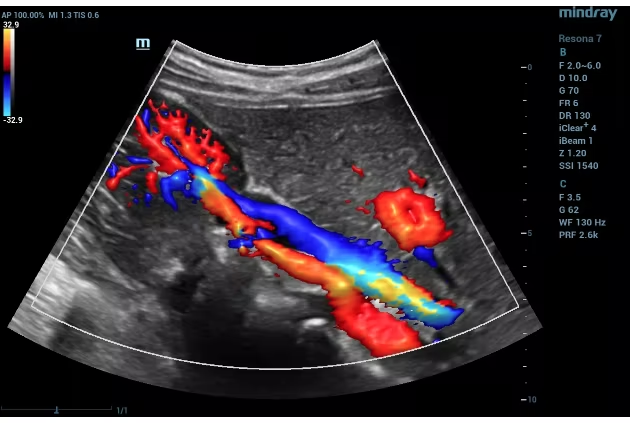

At Om Imaging Centre, we specialize in Sonography, Color Doppler, and X-ray services. Our goal is to deliver accurate and timely results, helping you and your healthcare provider make informed decisions. We strive to be the leading diagnostic imaging center in the region by offering exceptional care, advanced technology, and personalized attention.